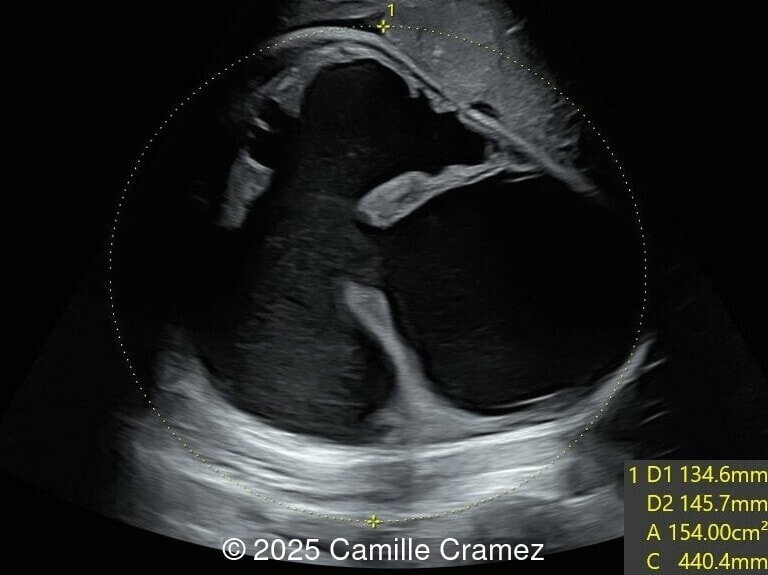

20-year-old primigravid woman, presented late for prenatal care at 29 weeks gestation. There was no consanguinity, and no pertinent past medical or familial history. We found the following anomalies:

Our prenatal ultrasound revealed a male fetus with megabladder, dilation of both ureter and kidneys, and thinned kidney parenchyma consistent with Lower Urinary Tract Obstruction (LUTO).  Additional findings suspected on ultrasound and confirmed on computed tomography included:

The diagnosis of PBS is often made in the second trimester of pregnancy, although it has been described as early as 11 weeks of gestation [20]. The most frequent ultrasound findings are a large, thin-walled bladder accompanied by bilateral hydroureter/hydronephrosis, dysplastic kidneys with echogenic renal parenchyma and renal cortical cysts, and abdominal wall laxity which is better viewed after bladder decompression [21]. Cryptorchidism can be detected prenatally by 28 to 30 weeks gestation when the testes descend into scrotum. There may be a patent urachus, visible as a cystic connection between bladder and umbilicus. Oligohydramnios is a frequent finding, which makes it difficult to visualize the associated anomalies.